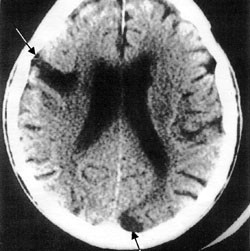

For å stille diagnosen vaskulær demens stilles det krav om påvisning av cerebrovaskulær sykdom på CT eller MR (1) (fig 2). Ved klinisk mistanke om vaskulær demens vektlegges bildemessige tegn til gjennomgått hjerneinfarkt og periventrikulære forandringer i hvit substans, og i henhold til ICD-10-kriteriene for vaskulær demens (2) skal det kunne påvises en tidsmessig sammenheng mellom et hjerneslag og utvikling av demenssymptomer. Patologiske funn av iskemiske forandringer på CT-caput kan gi indikasjon på cerebrovaskulær skade både i akuttfasen (13) og senere, men sensitiviteten for påvisning av fokale iskemiske forandringer er langt fra 100 %. En nyere klinisk-patologisk studie konkluderte med at cerebral CT bør brukes rutinemessig for å identifisere cerebrovaskulær sykdom som årsak til demens (14). Men fravær av nevroradiologisk patologi på cerebral CT er ikke ensbetydende med at cerebrovaskulære faktorer som årsak til demens kan utelukkes (15).